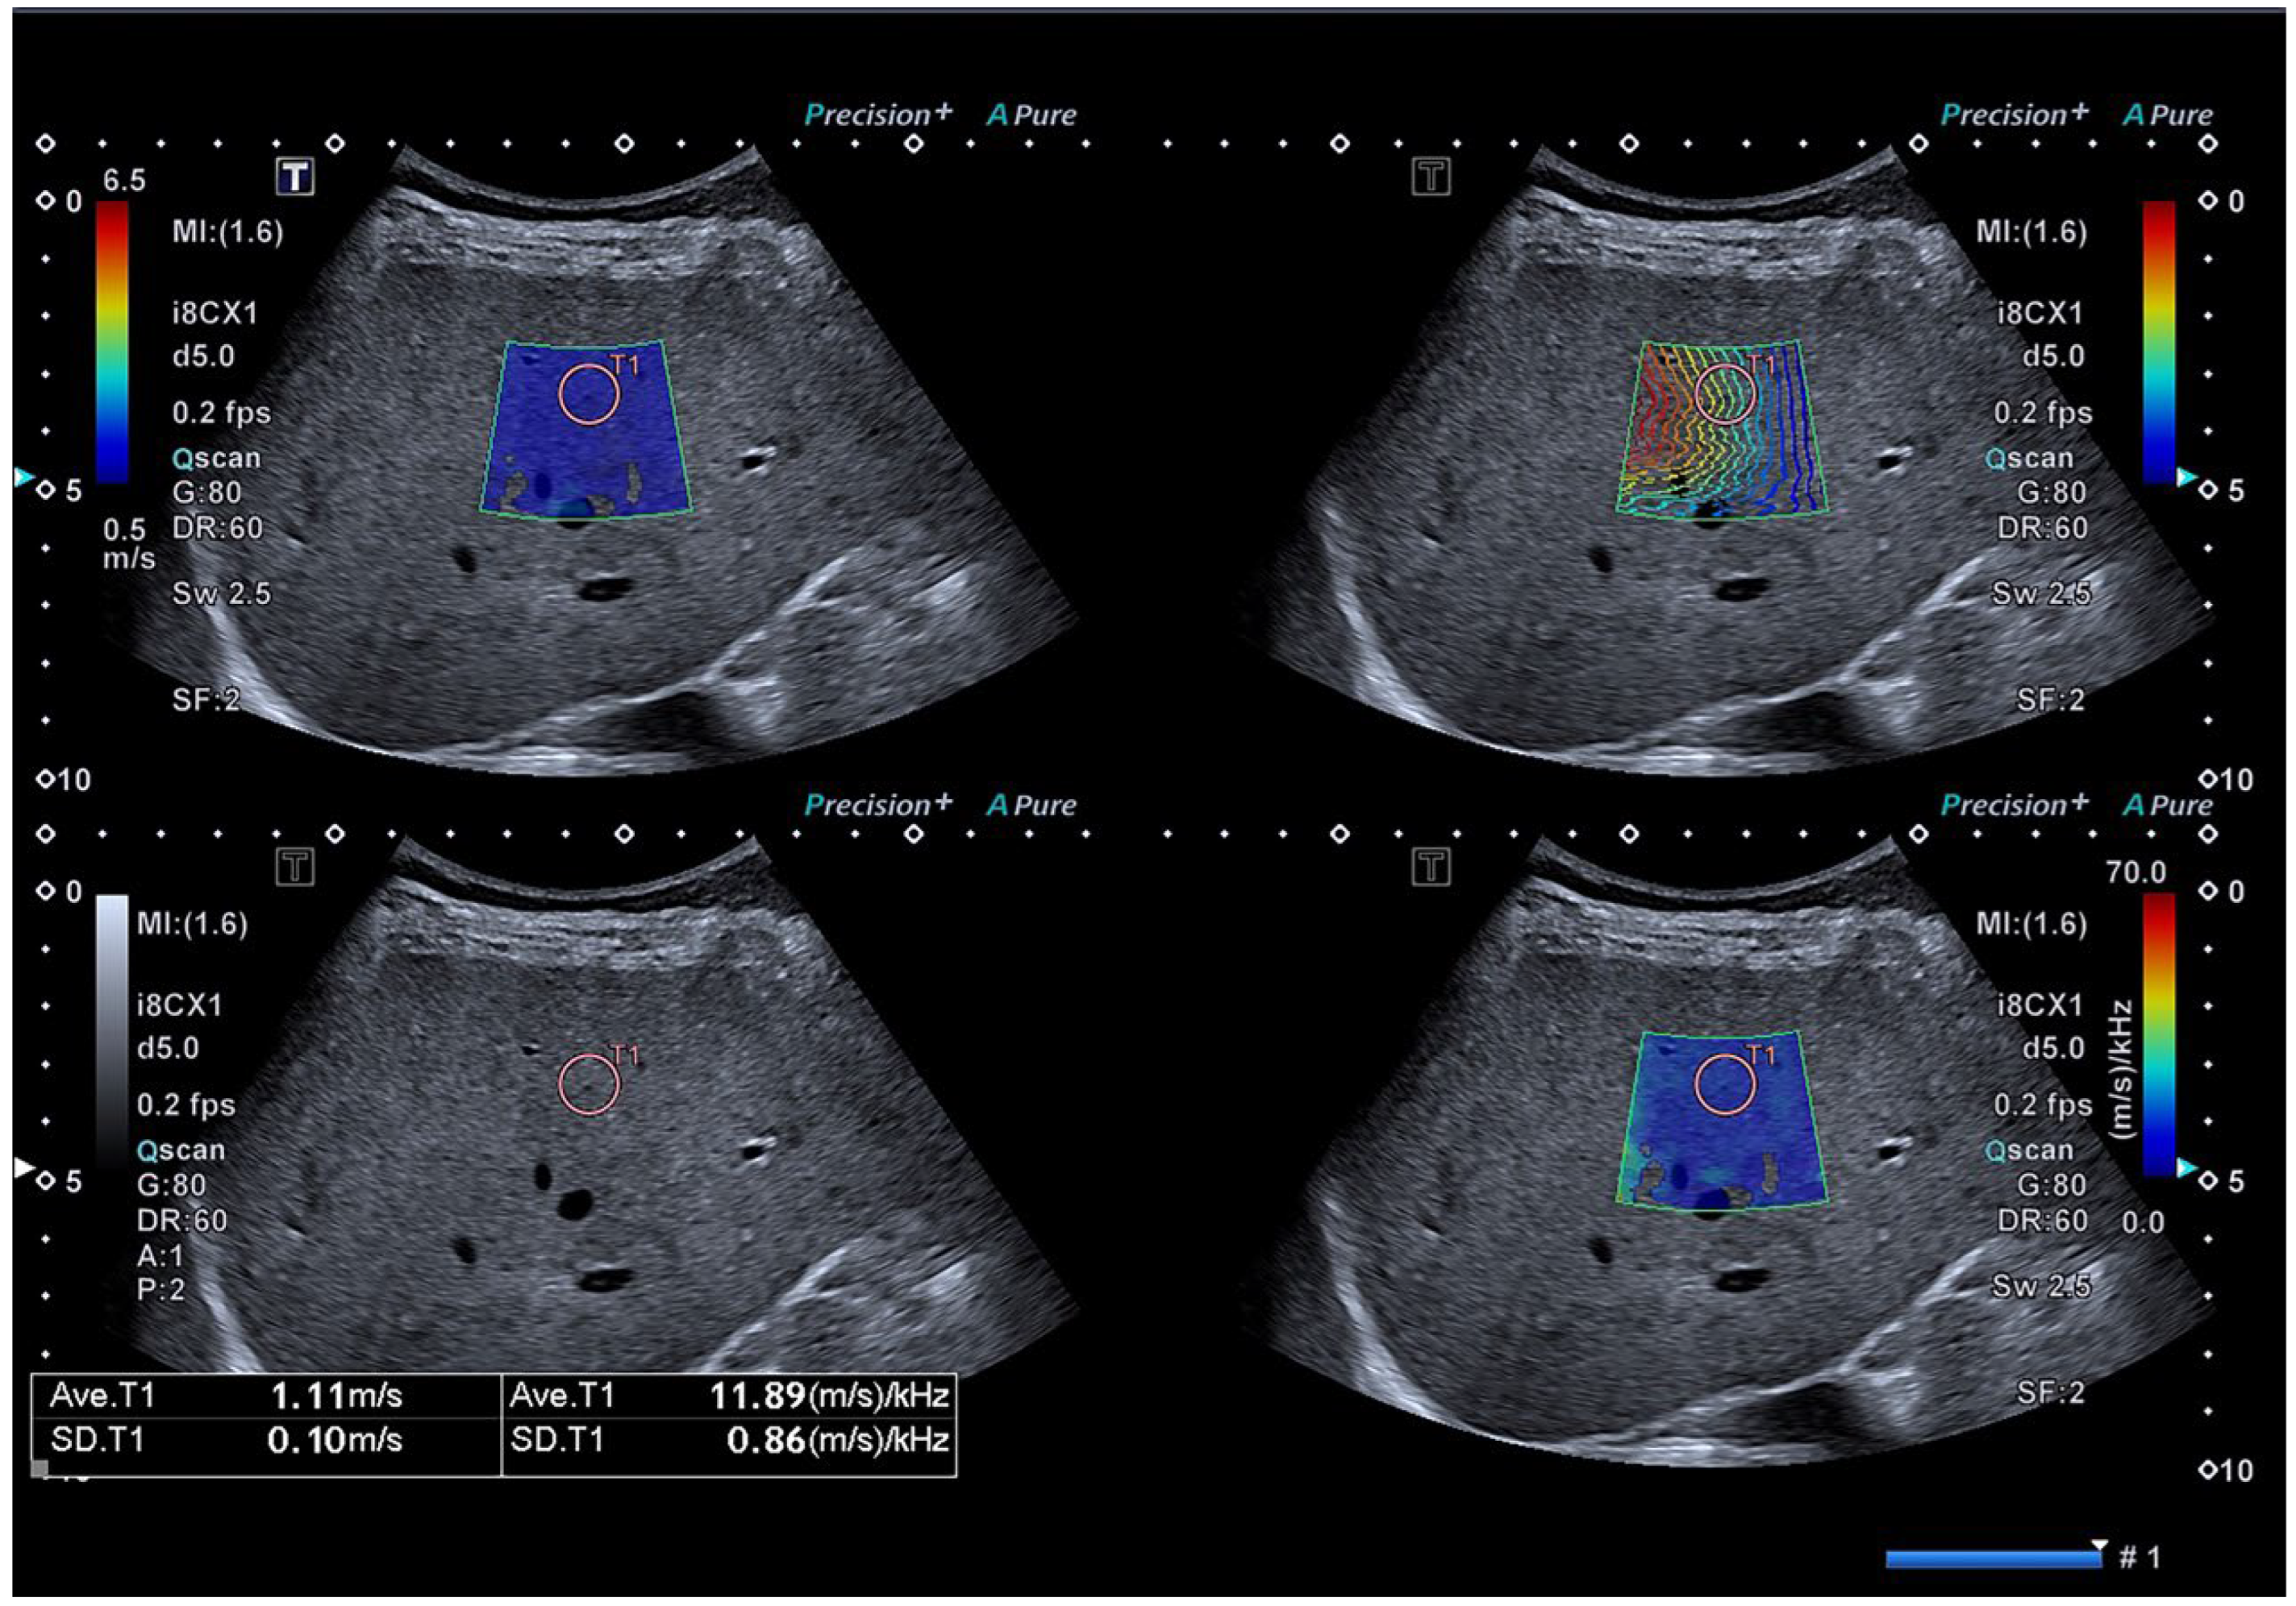

2.2. ATI, NLV and Ratio Examination

2.3. SWS and SWD Examination